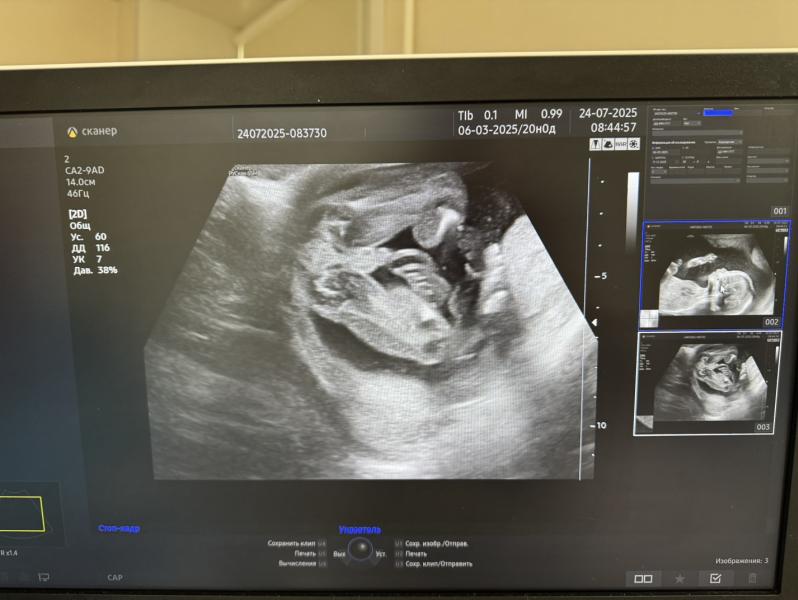

Сегодня прошли второй скрининг😍

В 17 недель была небольшая отслойка плаценты, сейчас уже все хорошо, на узи сказали, что вообще не заметно, что она была😄

Очень уж я ждала девочку🥹до такой степени, что у меня снова будет мальчик😄🥳но ни капли грусти, будут у меня два пацана, два моих защитника😎